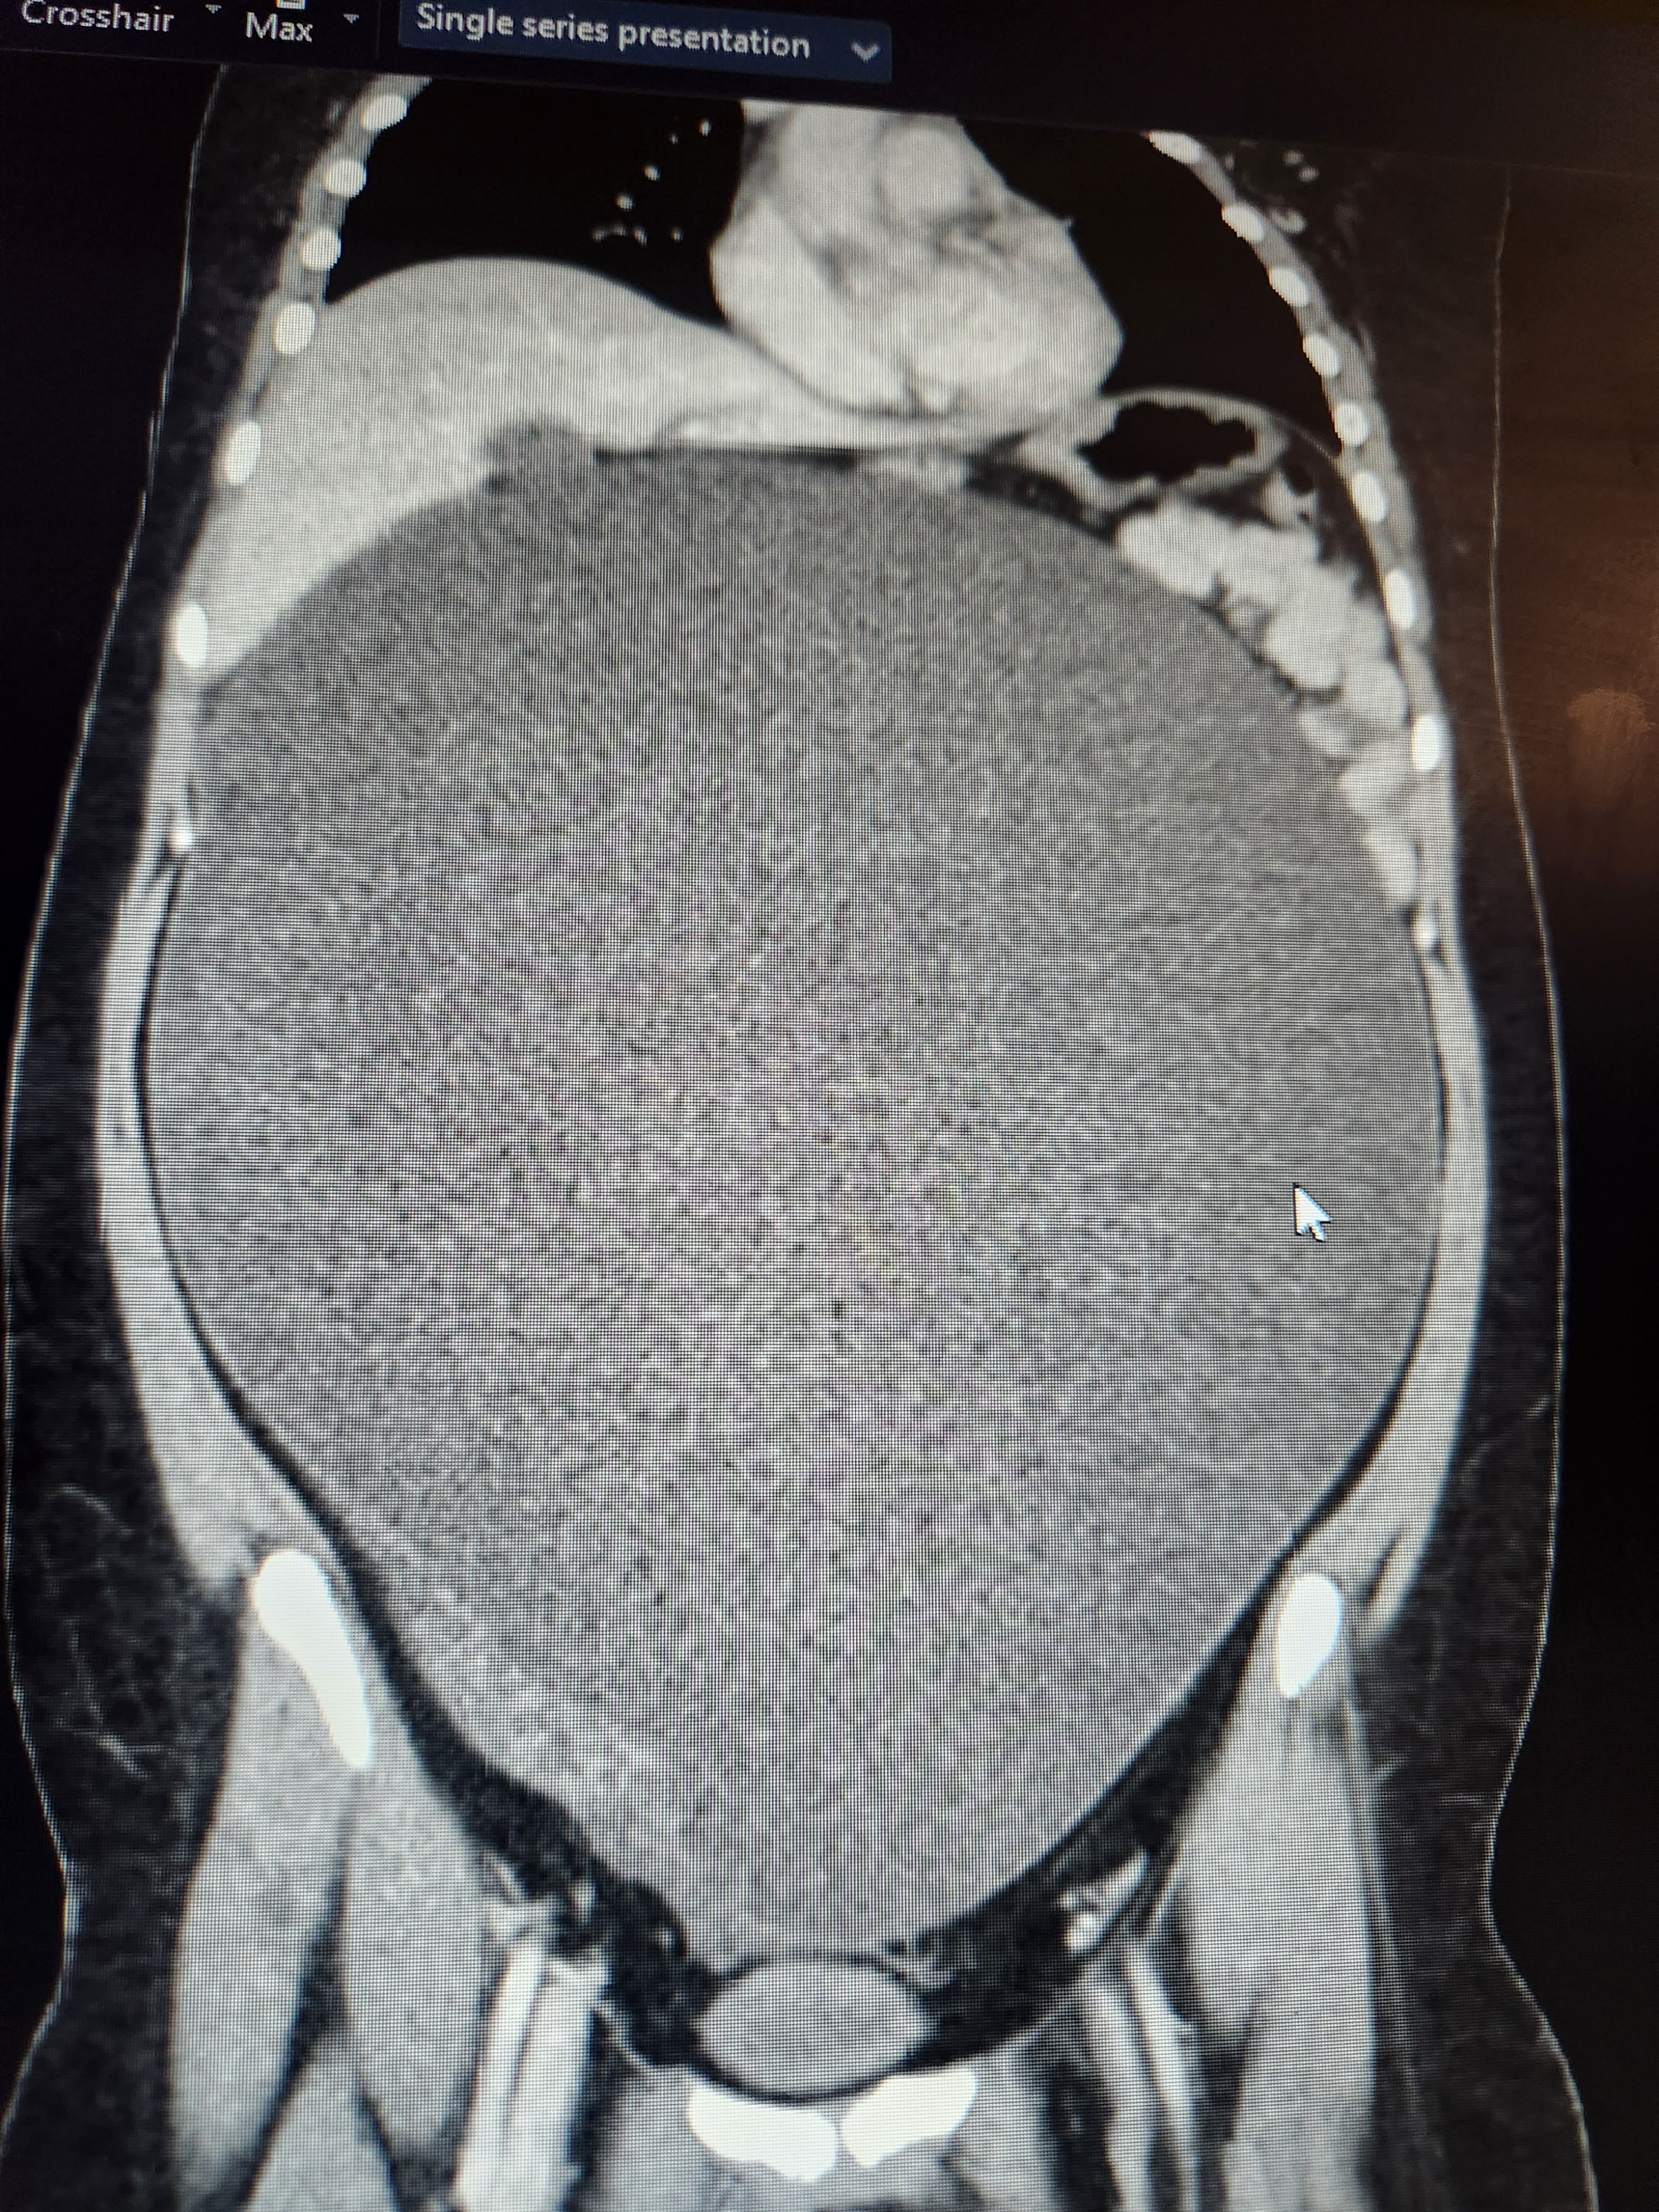

MANY hours in the local ER, labs, more labs, 3x ultrasounds, CT, pelvic & abdominal MRIs, consults with GYN, GYN/OC, hospitalists, GI, & urology... revealed Bella has a MASSIVE serous fluid-filled cyst (tumor) filling her ENTIRE ABDOMINAL CAVITY. It is pushing on the bottom of her heart & stretches down to her private area where it is completely compressing her Right ureter, causing R kidney backflow. Where her lower R ovary is she has a solid distended mass, most likely the malignant root of the larger cyst. Her stomach, liver, lungs & spleen are being pushed up & back towards her heart. Her intestines are severely compressed into her spine.

The Beast has made itself known. Very quickly it became obvious Bella's vomiting was hard to control (everything is being forced up) & her pain has increased dramatically as the mass has reached... critical mass on her organs. She can no longer eat or use the restroom, she can't lay down or the pressure-pain is excrutiating, & she struggles to breathe.